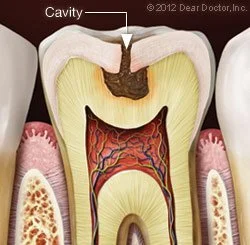

Fillings do just what the name implies — seal a small hole in your tooth, i.e., a cavity, caused by decay. This prevents the decay (a bacteria-induced infection) from spreading further into your tooth and, if untreated, continuing on to the sensitive inner pulp (nerve) tissue located in the root canal. Should that happen, you would need root canal treatment.